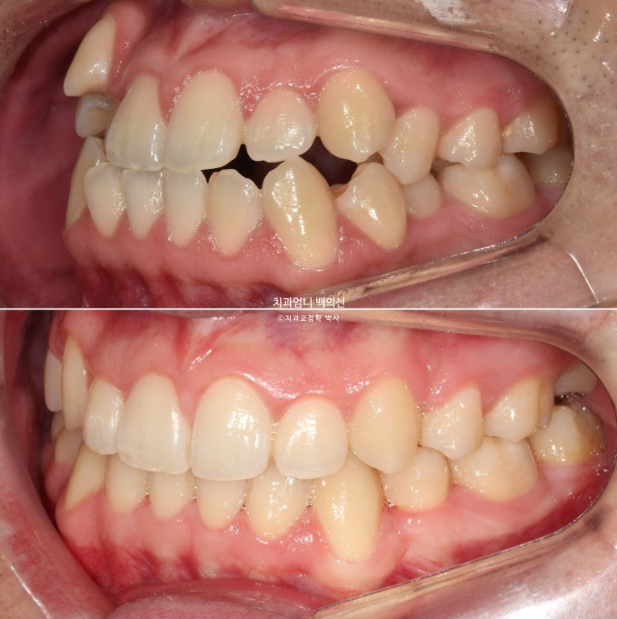

이제 전 후 비교 보겠습니다.

22.09~25.04